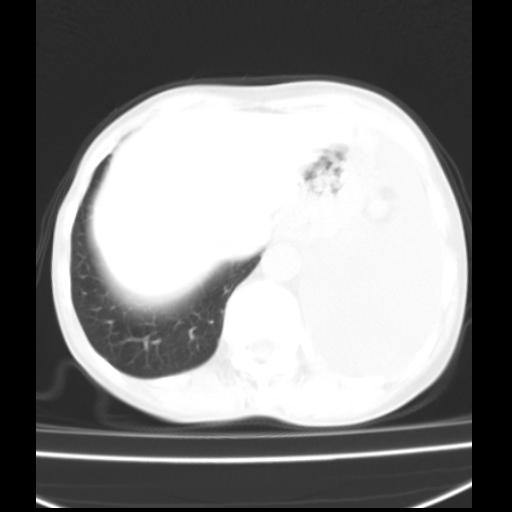

以下是引用随光逐影在2010-3-24 19:15:00的发言:[br]结合病史,考虑双肺及纵隔淋巴结多发转移、左侧胸膜转移并左侧大量胸水,左下肺膨胀不全。

以下是引用zxl51642在2010-3-24 18:49:00的发言:[br]结合乳腺癌术后病史,考虑双肺及纵隔淋巴结多发转移、左侧胸膜转移并左侧大量胸水、左下肺膨胀不全。